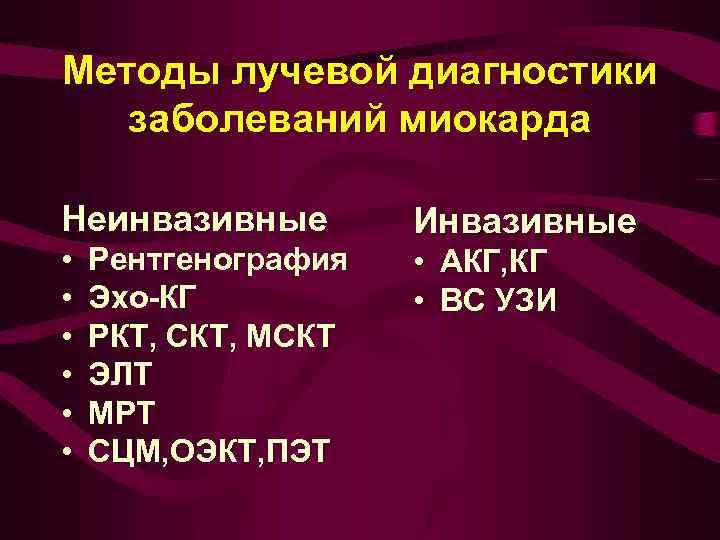

Методы лучевой диагностики заболеваний миокарда Неинвазивные • • • Рентгенография Эхо-КГ РКТ, СКТ, МСКТ ЭЛТ МРТ СЦМ, ОЭКТ, ПЭТ Инвазивные • АКГ, КГ • ВС УЗИ

Методы лучевой диагностики заболеваний миокарда Неинвазивные • • • Рентгенография Эхо-КГ РКТ, СКТ, МСКТ ЭЛТ МРТ СЦМ, ОЭКТ, ПЭТ Инвазивные • АКГ, КГ • ВС УЗИ